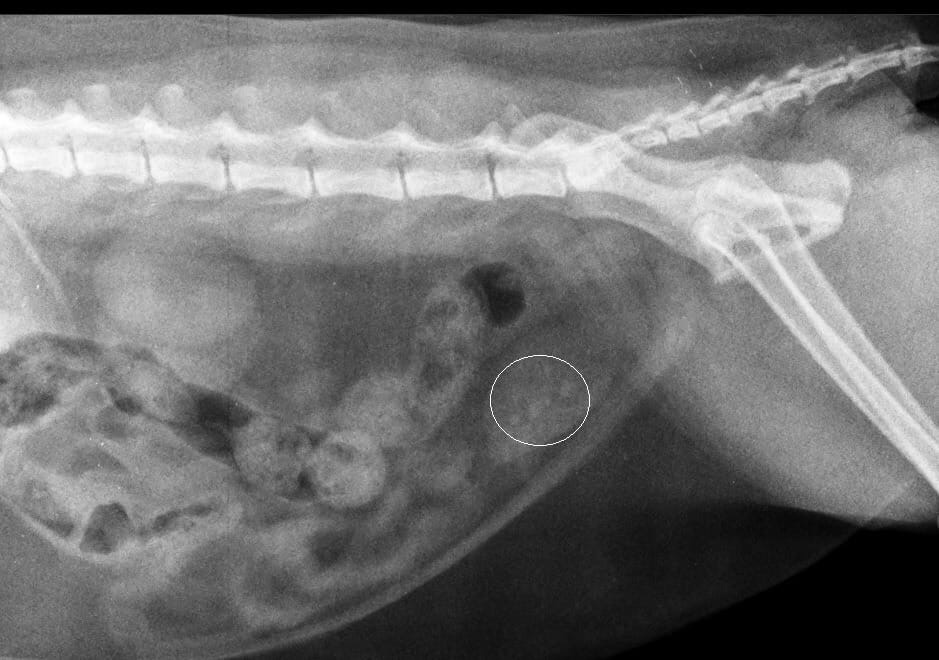

Точная диагностика и инновационное лечение мочекаменной болезни

Цистоскопия + дробление камней (литотрипсия): почему мы совмещаем диагностику и лечение за один визит

Стандартный сценарий при обнаружении камней в мочевом пузыре кошки — это диагноз «по УЗИ», затем тяжелая полостная операция (цистотомия) с разрезами, швами и долгим восстановлением. А если камень не один? А если это не камень, а опухоль? Мы уходим от этой лотереи

- Точный диагноз. Не «камень похож на оксалат», а «это струвитный камень размером 4 мм с рыхлой структурой». Или «это не камень, а полип».

- Оценку состояния слизистой. Врач видит степень воспаления, кровотечения, предраковые изменения.

- Возможность биопсии. При необходимости можно сразу взять образец ткани для анализа.

Лазерная литотрипсия

Как только диагноз «камень, требующий удаления» подтвержден, врач не достаёт эндоскоп. Он меняет насадку и проводит через рабочий канал того же прибора датчик литотриптора.

- Как это работает: Под прямым визуальным контролем зонд прибора точечно воздействует на камень, дробя его до состояния мелкого песка («пыли»), который затем вымывается или выводится естественным путем.

- Ключевое преимущество: Лечение мочекаменной болезни проводится сразу, в ходе той же самой процедуры, под той же анестезией. Не нужно дважды готовить животное к наркозу, дважды везти в клинику.